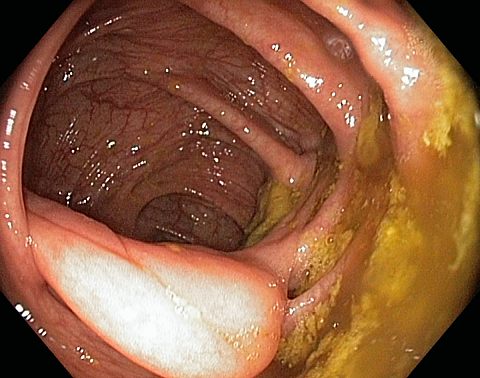

Ileocaecal valve